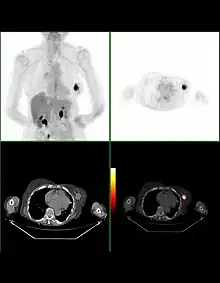

Bilan d'extension

La recherche de métastases est fondamentale dans la stratégie du traitement du cancer du sein. Mais, malgré les nombreuses études réalisées ou la connaissance approfondie de certaines explorations, il n'existe actuellement aucune stratégie validée de recherche systématique de métastase dans le cancer du sein.

La plupart des recommandations proposent actuellement un bilan d'extension comportant un examen clinique soigneux à la recherche de métastases ganglionnaires, une radiographie thoracique, une échographie hépatique et une scintigraphie osseuse. Pour les tumeurs de très petite taille, ce bilan peut être facultatif. En revanche, pour les tumeurs évoluées (tumeurs inflammatoires, multi-focales, envahissement ganglionnaire important), le risque métastatique initial est élevé et peut justifier un bilan plus poussé comportant une Tomodensitométrie (TDM) corps entier et une IRM mammaire.

La taille de la tumeur, l'existence d'adénopathies métastatiques, l'existence d'une atteinte de la peau ou de la paroi thoracique ou de métastases à distance permettent d'établir une classification clinique des cancers du sein.

Le bilan d’extension permet de classer le cancer selon la classification TNM qui prend en compte la taille de la tumeur, l'absence ou le nombre de ganglions atteints par le cancer et l'existence ou non de métastase. Cette classification est un des critères pour la prise en charge de la maladie.